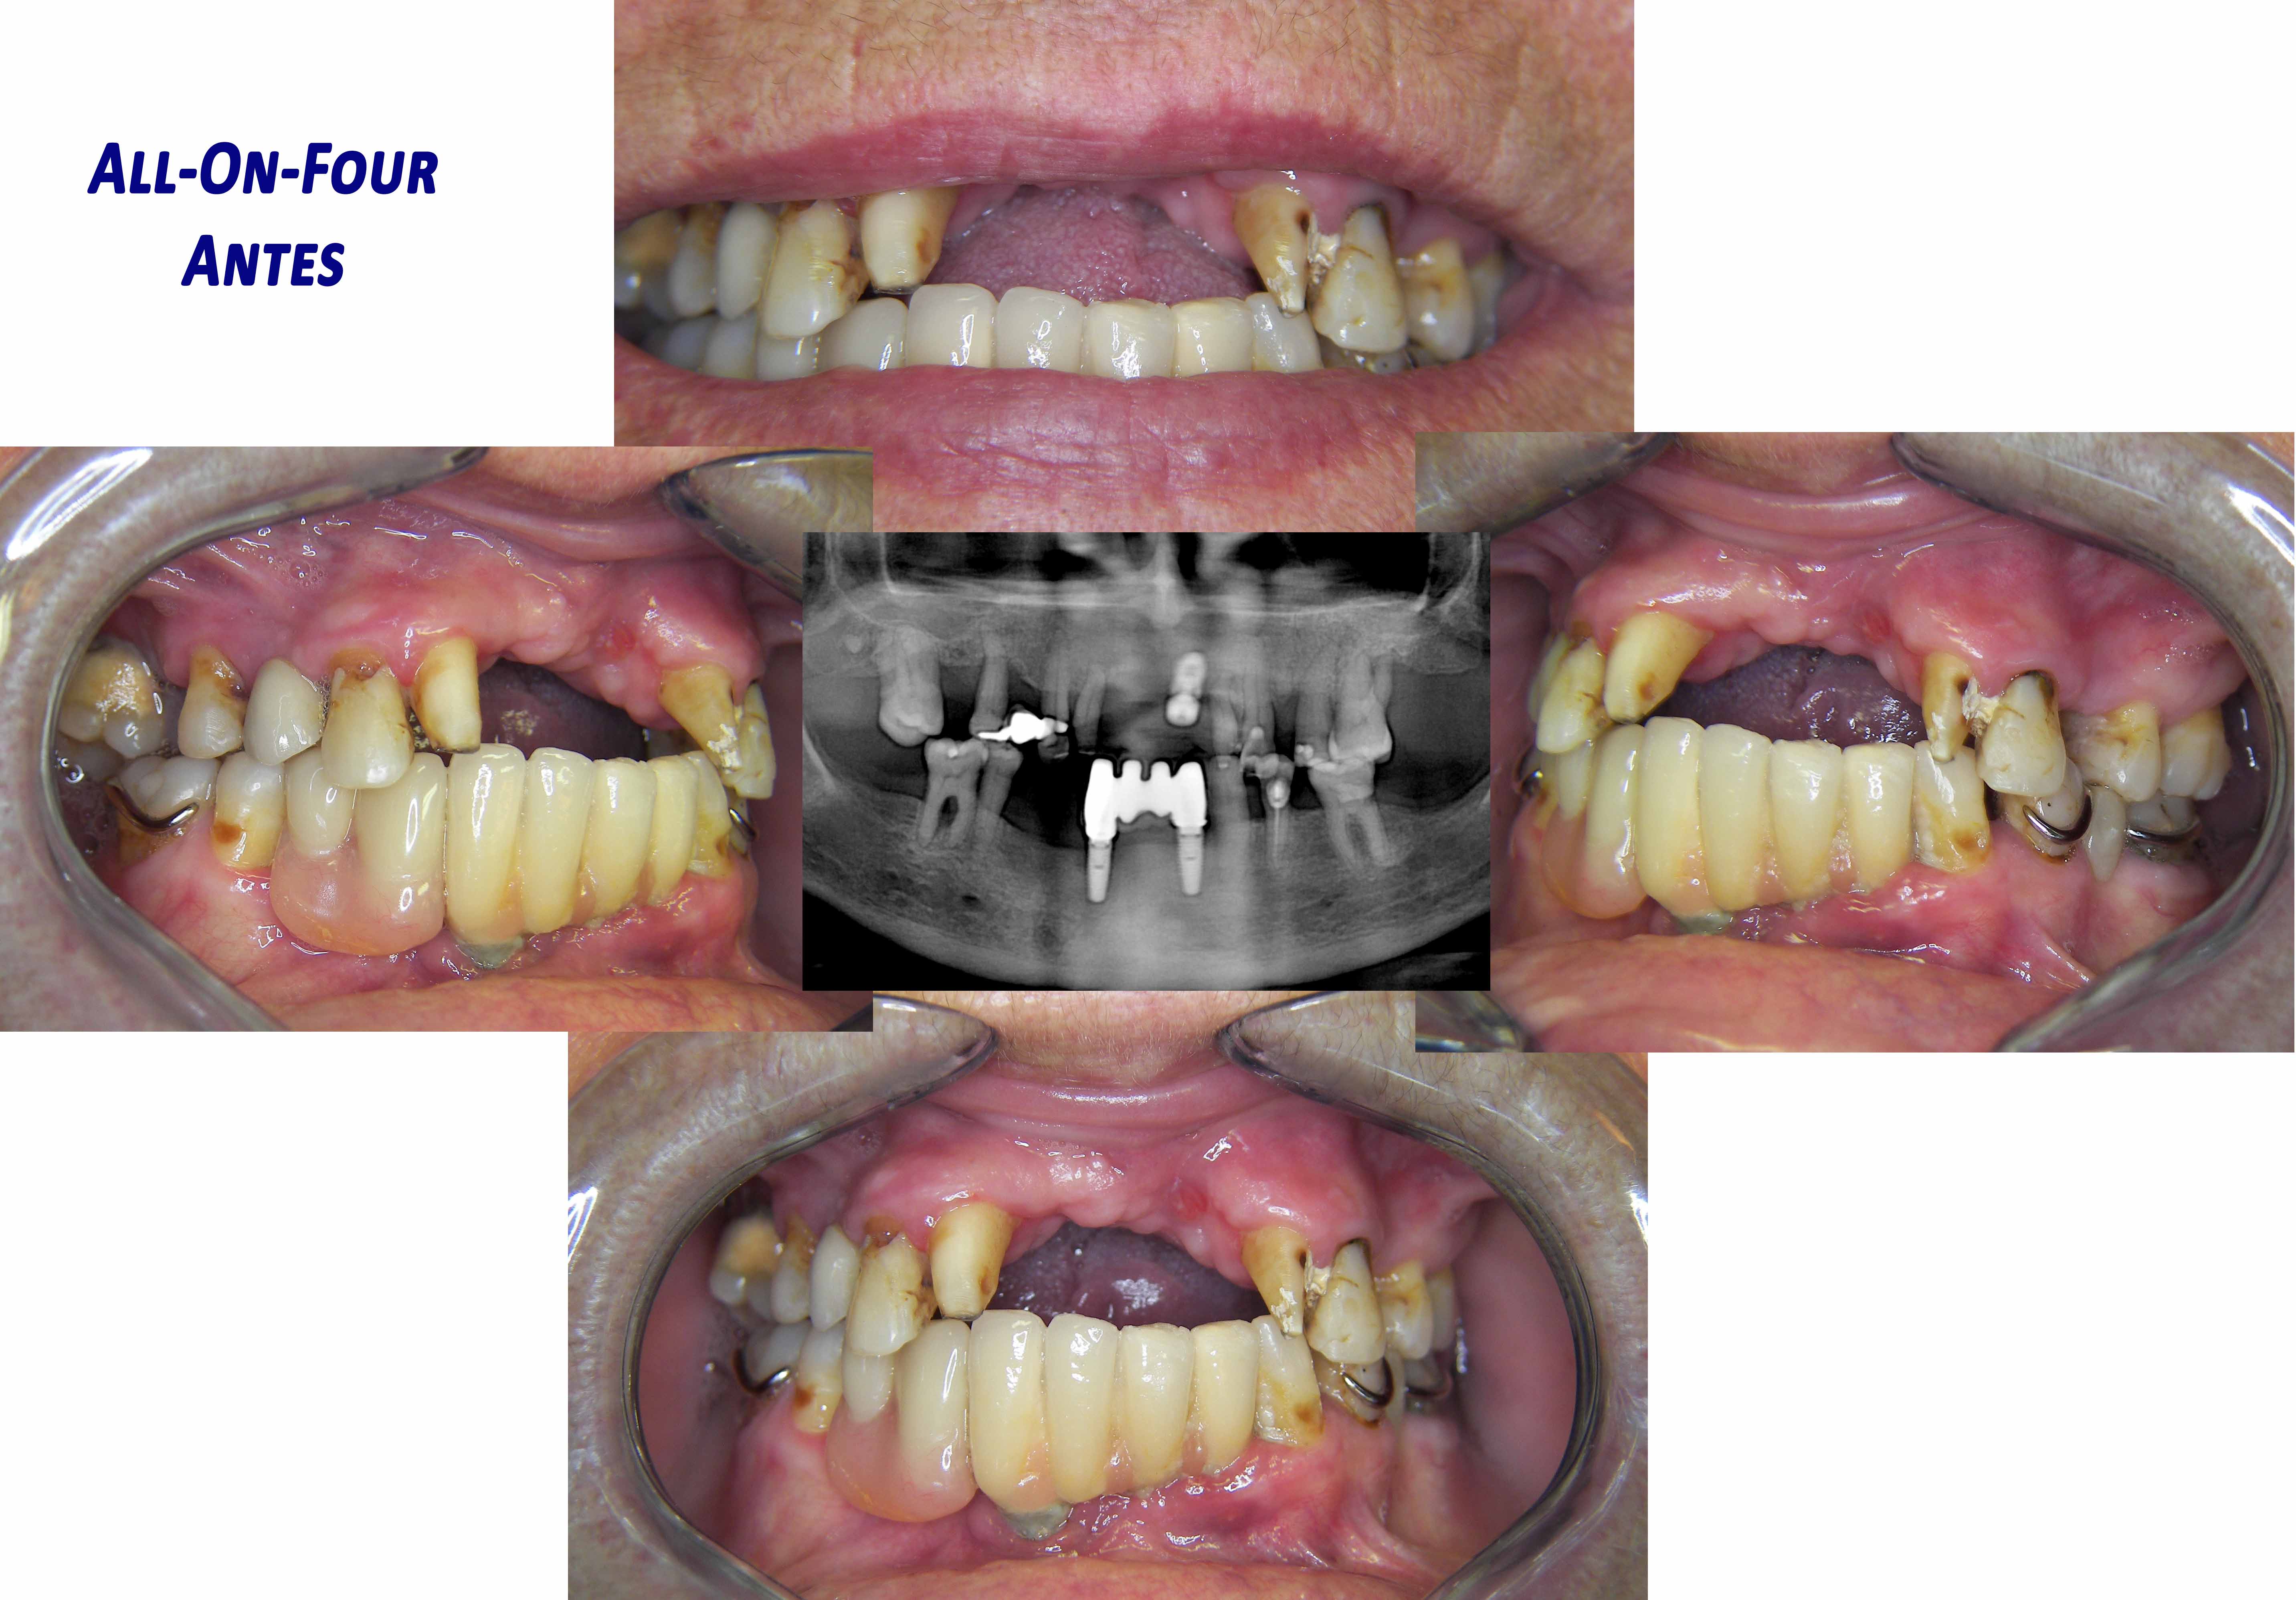

All-On-Four

Prótese Total sobre implantes de ambos os maxilares. Pode se feita apenas num dos maxilares.

Este protocolo que utiliza 4 implantes por maxilar, permite a colocação de proteses provisórias fixas imediatas, no dia da cirurgia.